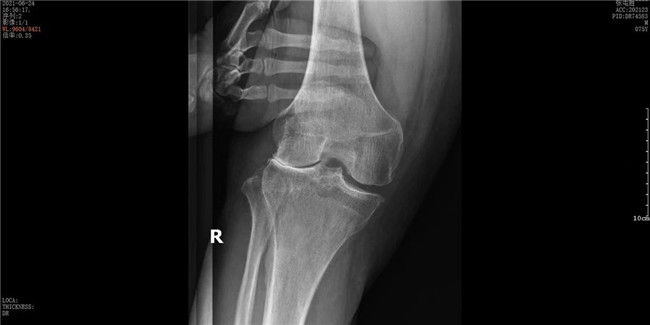

▲右膝關(guān)節(jié)外側(cè)間室磨損▲

接診后羅軍主任詳細(xì)檢查病人,發(fā)現(xiàn)病人疼痛癥狀主要集中在膝關(guān)節(jié)外側(cè)間室,右下肢有明顯外翻畸形。這些癥狀都是單髁置換的適應(yīng)癥。雙下肢全長(zhǎng)攝片和右膝內(nèi)翻、外翻位攝片顯示,膝關(guān)節(jié)外側(cè)間隙消失,膝外翻畸形,果不其然印證了上述臨床表現(xiàn)。收治入院后,羅主任團(tuán)隊(duì)決定為患者實(shí)施微創(chuàng)膝關(guān)節(jié)外側(cè)單髁置換術(shù),盡全力為張大爺解除病痛的折磨。